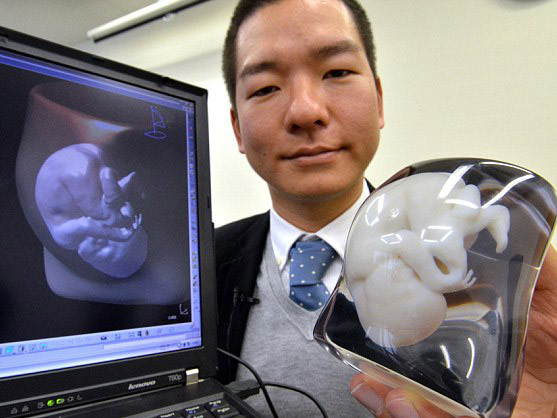

| Mô hình ba chiều của một bào thai được tạo nên nhờ công nghệ in 3D. |

Công ty FASOTEC đã tạo nên mô hình của các thai nhi bằng công nghệ in 3D. Việc dựng mô hình 3 chiều này tương tự như quá trình siêu âm song thay vào đó là dùng máy quét MRI (máy quét cộng hưởng từ).

Công nghệ in 3D này được sử dụng đối với các bào thai từ tám tháng tuổi trở lên.